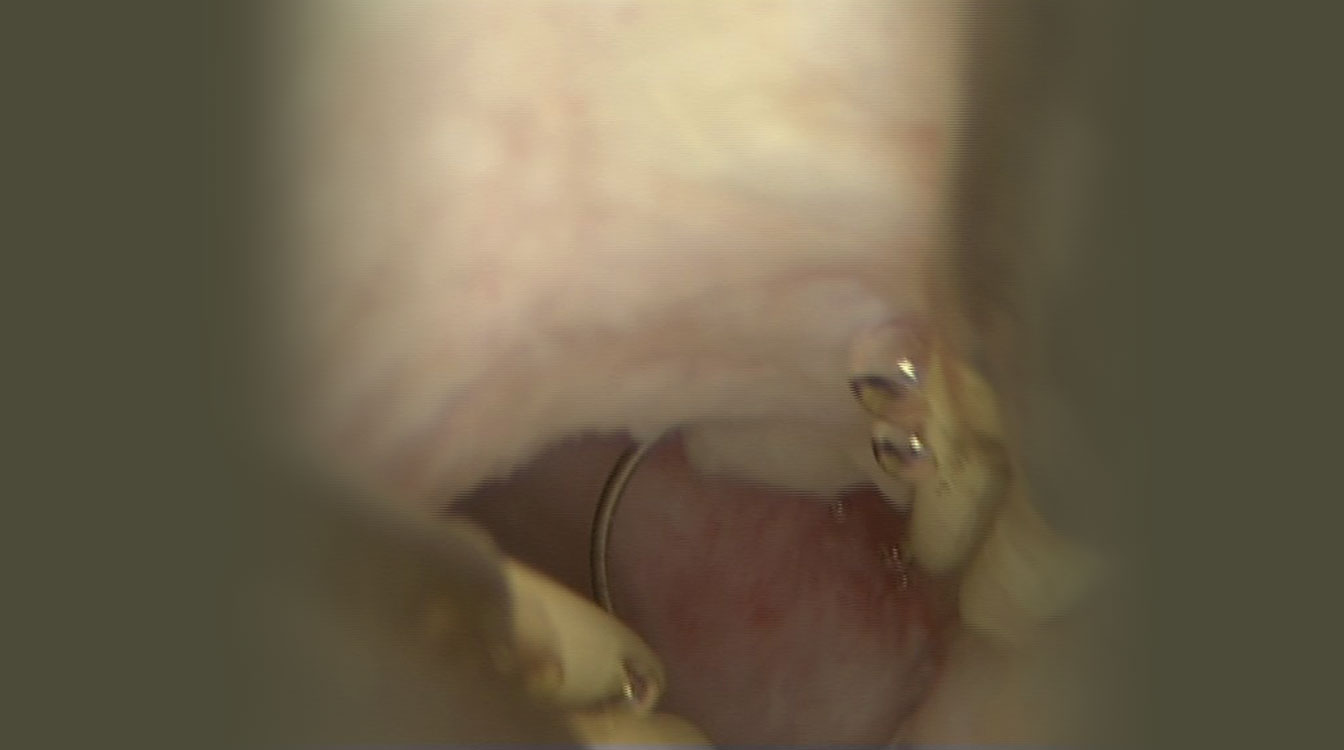

Fibroamele pot fi rezecate în fragmente mici, cu ajutorul unor anse electrice în cadrul histeroscopiei, procedeu numit rezectoscopie (fig. 6). Fragmentele rezecate sunt colectate din cavitatea uterină și trimise la laboratorul de anatomie – patologică pentru diagnostic histologic. Cavitatea uterină are aspect normal după operație, crescând foarte mult probabilitatea unei sarcini reușite.